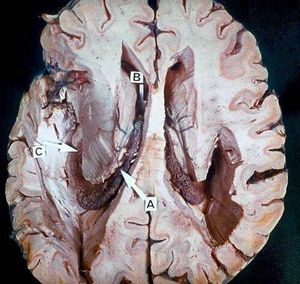

The Brain.A - Choroid plexus; B - Interventricular foramen; C - Choroid plexus in inferior horn of lateral ventricle.